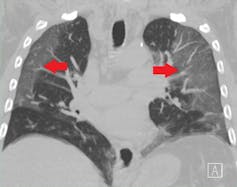

This Wuhan study was particularly interesting because the researchers used objective measures to evaluate the people reporting lingering symptoms. People in the study were still reporting persistent breathing problems six months after getting sick. When researchers performed CT scans to look at the patients’ lungs, many of the scans showed splotches called ground-glass opacities. These likely represent inflammation where SARS-CoV-2 had caused viral pneumonia. Additionally, the people in this study who had severe COVID-19 could not walk as fast as those whose illnesses were less severe – these lung problems reduced how much oxygen was moving from their lungs into their bloodstream. And remember, this was all measured six months after infection.